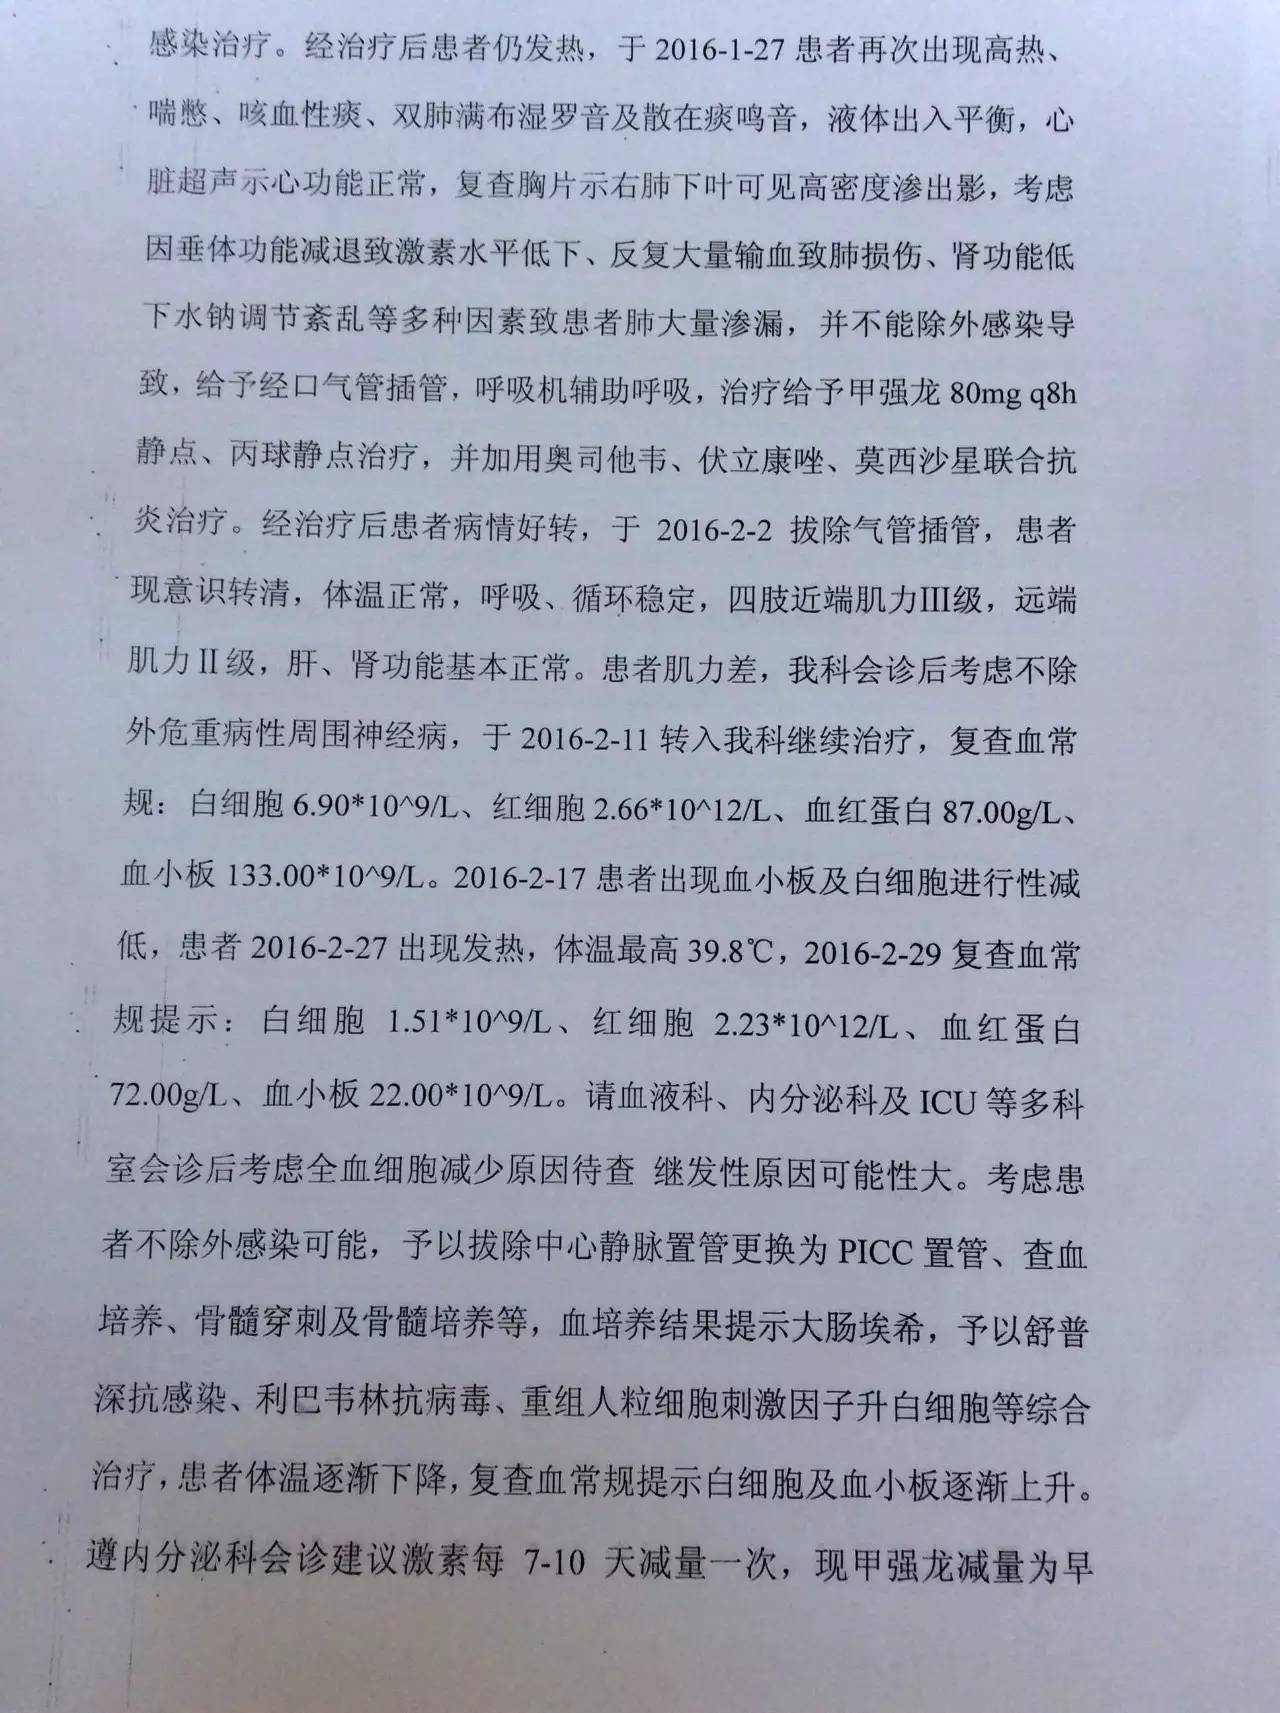

▼患者病程记录资料

目前患者面临的问题是出现了甲状腺功能减退症和肾上腺激素需要减量的问题。结合患者产后一系列的意外和抢救过程,要警惕患者出现Sheehan syndrome(希恩综合征),因为低血压、出血等等引起垂体缺血缺氧所致。

1.甲状腺功能减退症:因为患者属于继发性甲状腺功能减退症,因此根据FT4水平来调整优甲乐的剂量即可,目前加量到100μg/天,同意这种调整;

2.患者应用甲强龙,当时是因为出现了休克为了抢救所用,目前情况明细好转,可以每周(也就是贵院内分泌大夫会诊的7~10天)减量甲强龙1片(4mg); 但因为患者可能存在继发性肾上腺皮质功能减退症(继发于希恩综合征),减量到全天2片时需要评估清晨未服药前ACTH和血皮质醇、电解质、性腺激素六项来评估是否能够完全停药,还是需要减成替代剂量,此时可以应用泼尼松来替代甲强龙,泼尼松一片是5mg,等效于甲强龙1片,4mg,如果确实出现肾上腺皮质功能减退,可以逐渐减量到泼尼松全天1片(2.5mg,早上和下午各服用一片)。到时候再根据患者复查的情况判断肾上腺功能的恢复情况。